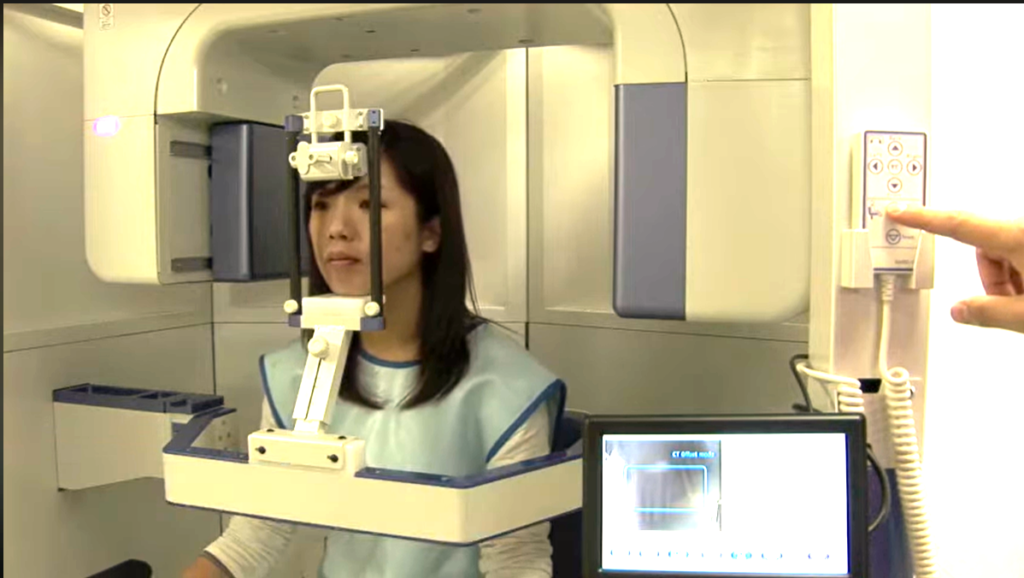

CT撮影による3D事前診断

危険な神経を正確に診断